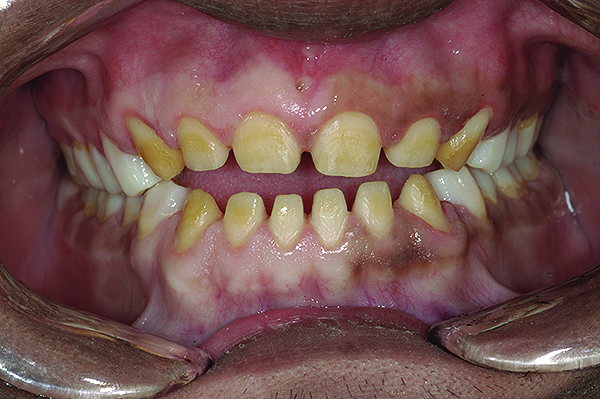

Figure 2. Preoperative 1:2 retracted frontal view.

Figure 2

The authors report on a 21-year-old patient who presented with severe discoloration and mild sensitivity of teeth (Figure 1). The teeth visible in his smile were very short, unsightly, and unbecoming for his age.

A thorough clinical examination and analysis were carried out to assess the esthetic and functional problems of the patient (Figure 2 through Figure 7). The medical history was non-contributory, except for mild leukoderma. Temporomandibular joint (TMJ) function was within normal range.

Mounted study casts were used to evaluate occlusion. The relevant findings were as follows2: Facial analysis revealed a canted maxillary occlusal plane and canted dental midline. Dentolabial analysis showed that the maxillary incisors were not adequately visible during repose; it also revealed a reverse smile line, as well as a wide smile showing 12 teeth. Results from the phonetic analysis were that “F” and “V” sounds revealed upper incisal shortening, “M” and “S” pronunciation disclosed a diminished vertical dimension of occlusion (VDO), and “E” sounds showed severe shortening of incisors. Dental analysis revealed thick biotype, asymmetry and inappropriate location of gingival levels and zenith, incorrect axial inclinations, a displeasing width-to-length ratio, and pitted surfaces on most teeth. Interproximal decay was evident on several posterior teeth, as revealed by radiographic analysis. Finally, occlusal examination indicated discrepancy between maximum intercuspation (MIP) and centric relation (CR) as well as a lack of anterior guidance/posterior disclusion.